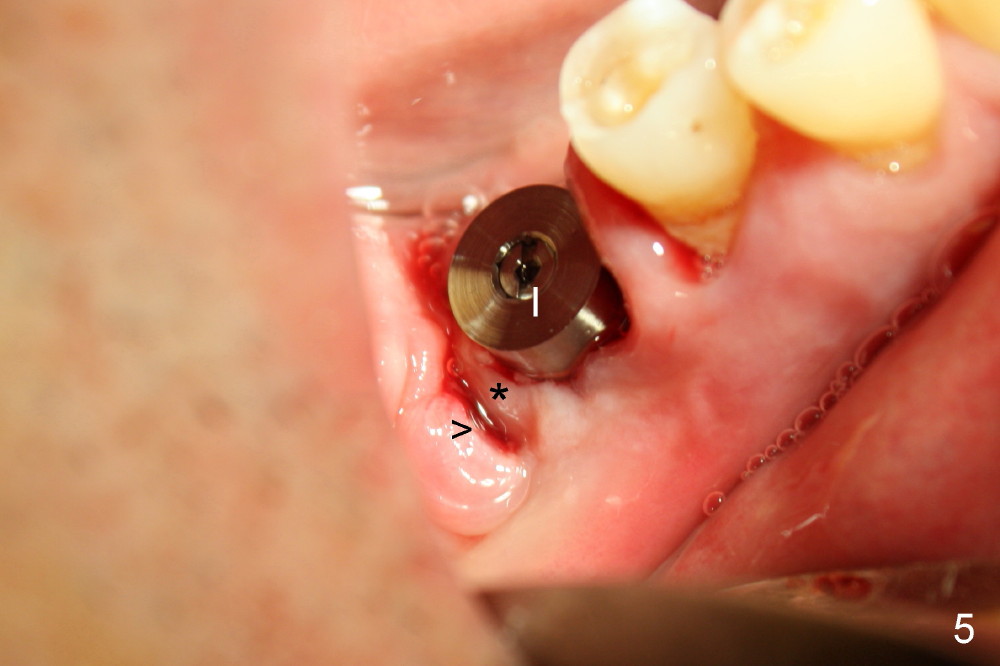

Drills are used to change osteotomy created by osteotomes more buccally. Taps are also applied. When 5x17 tapered implant (Fig.5 I) is inserted with torque >60 Ncm, the furcal gingiva (*) is further advanced distally to close DB socket (Fig.5 >) and DL one (Fig.6 <).